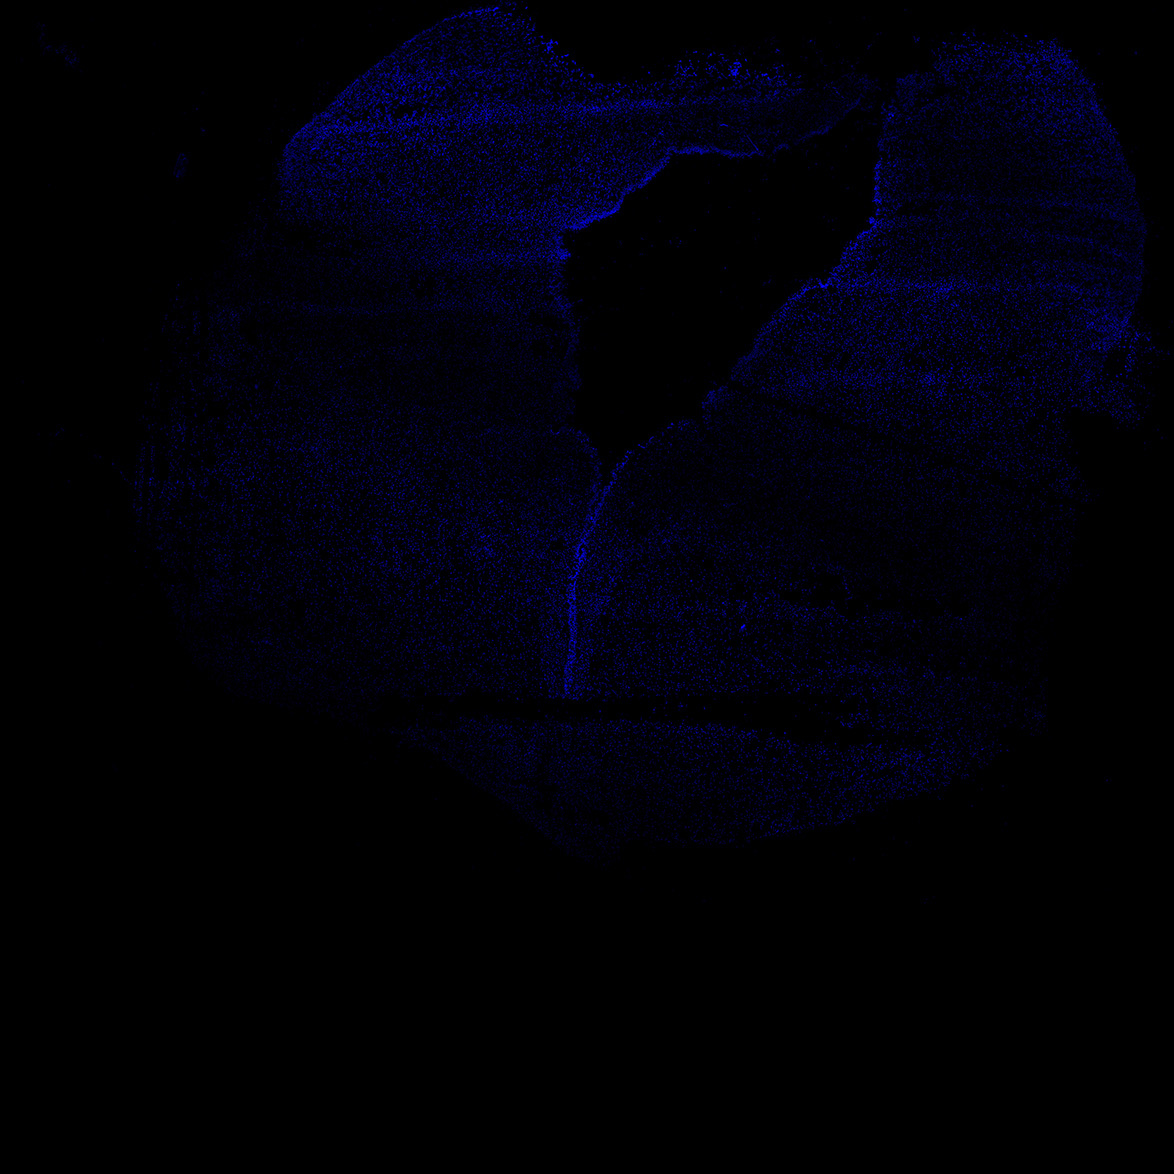

DAPI

6PCW human midbrain